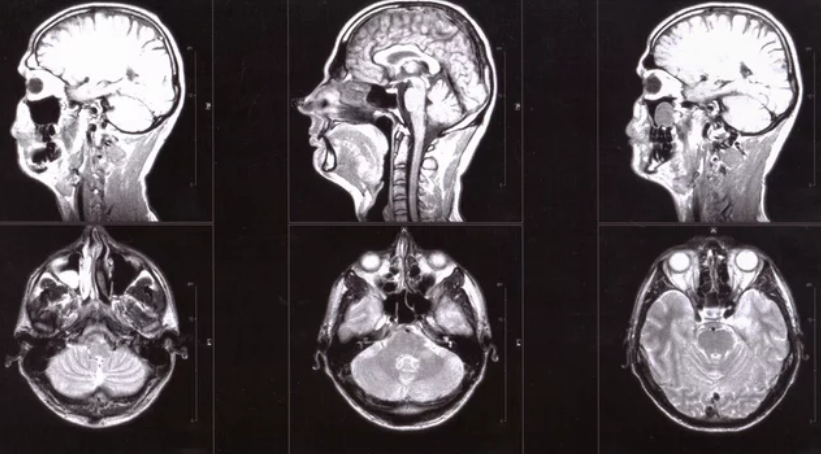

Magnetic Resonance Imaging (MRI) has evolved from a diagnostic luxury into a cornerstone of modern medicine. Its unmatched ability to visualize soft tissues, monitor treatment, and detect diseases early has revolutionized healthcare delivery. Yet, as MRI technology advances—becoming faster, smarter, and more accessible—it also reshapes the policies that govern healthcare systems worldwide.